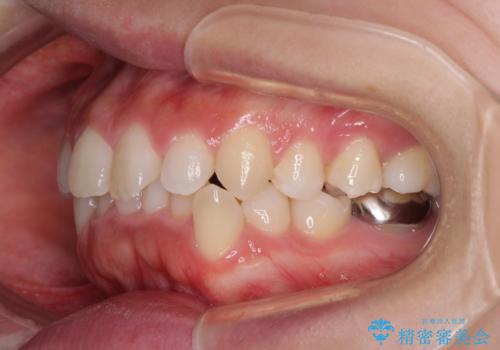

- 前歯のデコボコやクロスバイト、口元の突出感を気にして来院された患者様です。

上下左右の第一小臼歯4本を抜歯して、ワイヤー装置にて矯正治療を行うこととしました。